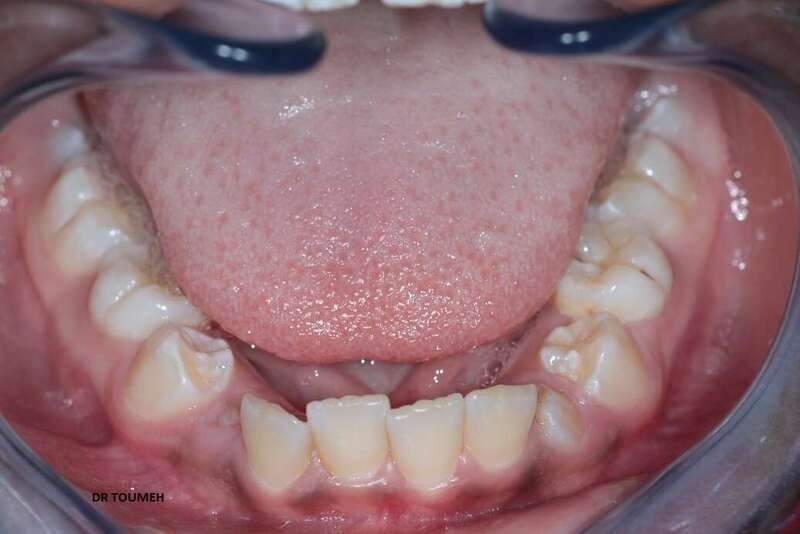

Avant

Après